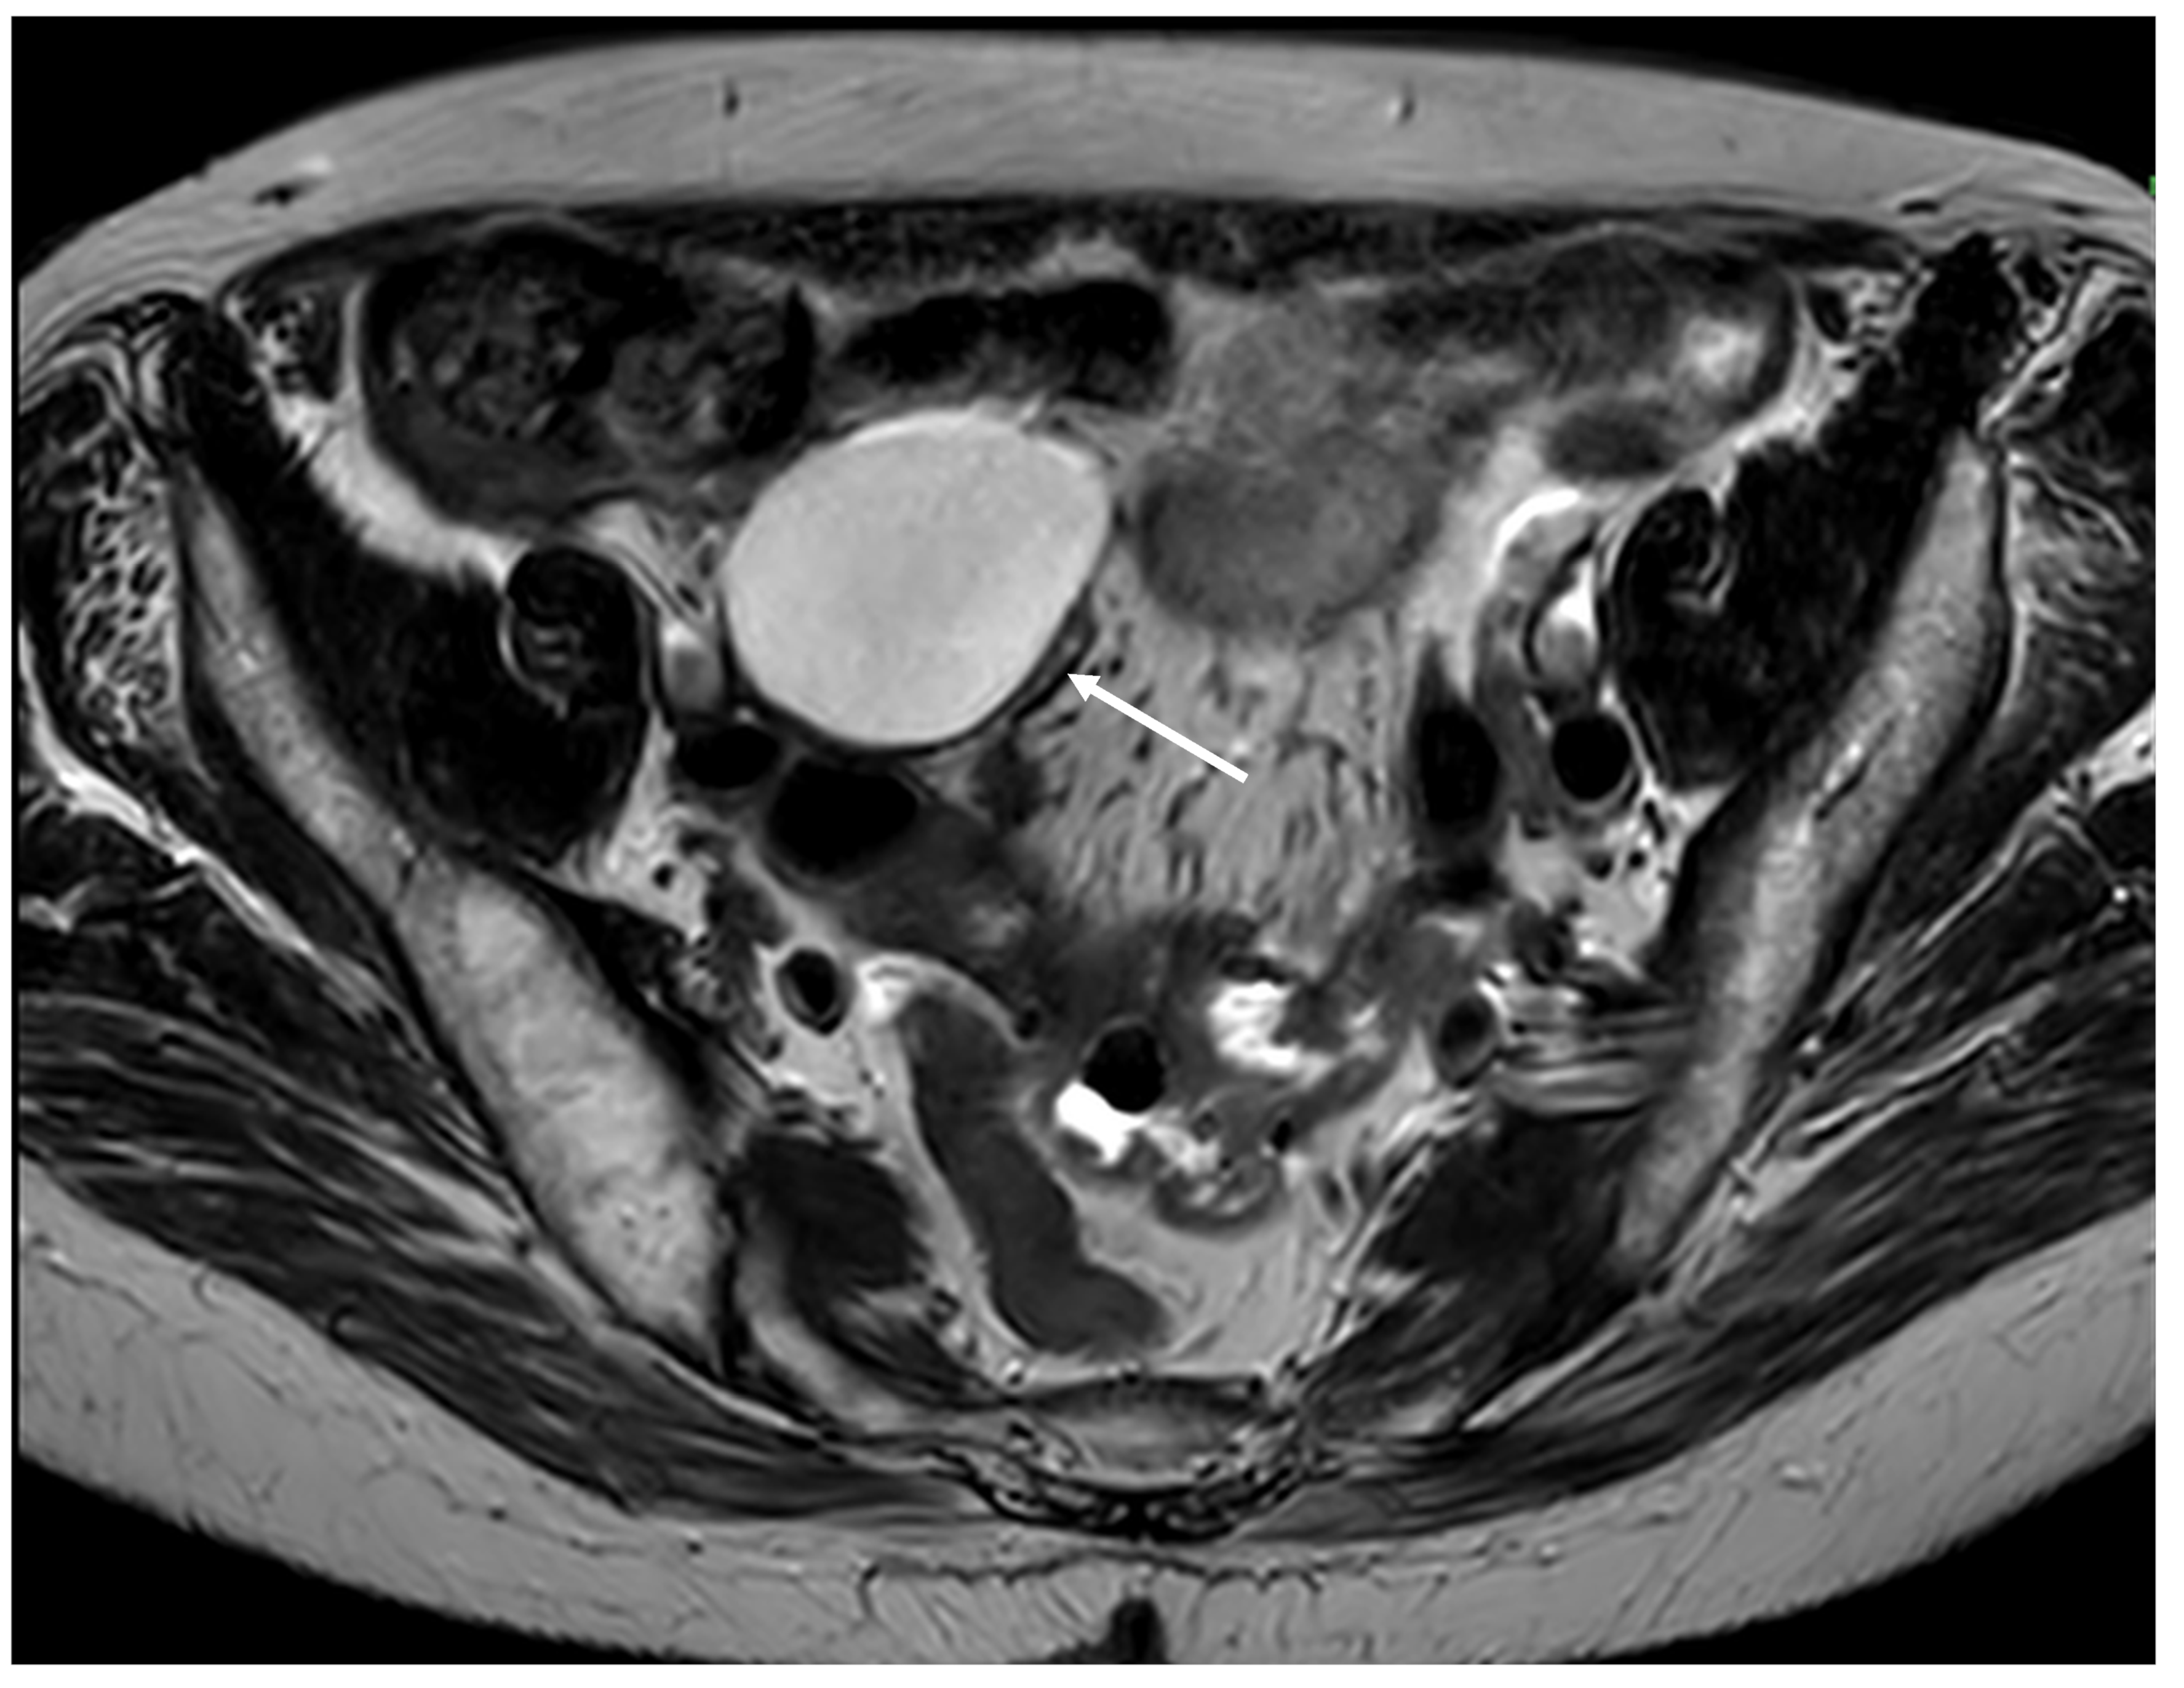

Figure 4. Cystic dilatation of the appendix (mucocele) (arrow) (MRI, axial plane).

Mucocele of the appendix refers to a dilated mucin-containing appendix. This term is mainly used by clinicians and radiologists (Figure 1, Figure 2, Figure 3 and Figure 4). It is necessary to distinguish “true mucocele” from a mucinous adenoid neoplasm [7]. The term mucocele was first used by Karl Freiherr von Rokitansky in 1842. Two years later, Werth used the term pseudomyxoma peritonei [4]. The clinical signs are minimal or often completely absent. The rupture of the mucocele can also be asymptomatic. Mucocele may be found on ultrasound or via a regular gynecological examination. A CT scan confirms the diagnosis. Treatment consists of the surgical removal of the dilated appendix, often together with the surrounding part of the cecum (Figure 5, Figure 6 and Figure 7). This approach is curative if there is no rupture or presence of tumor cells on the peritoneal surface. The diagnosis is confirmed through pathological examination of the specimen (Figure 8).